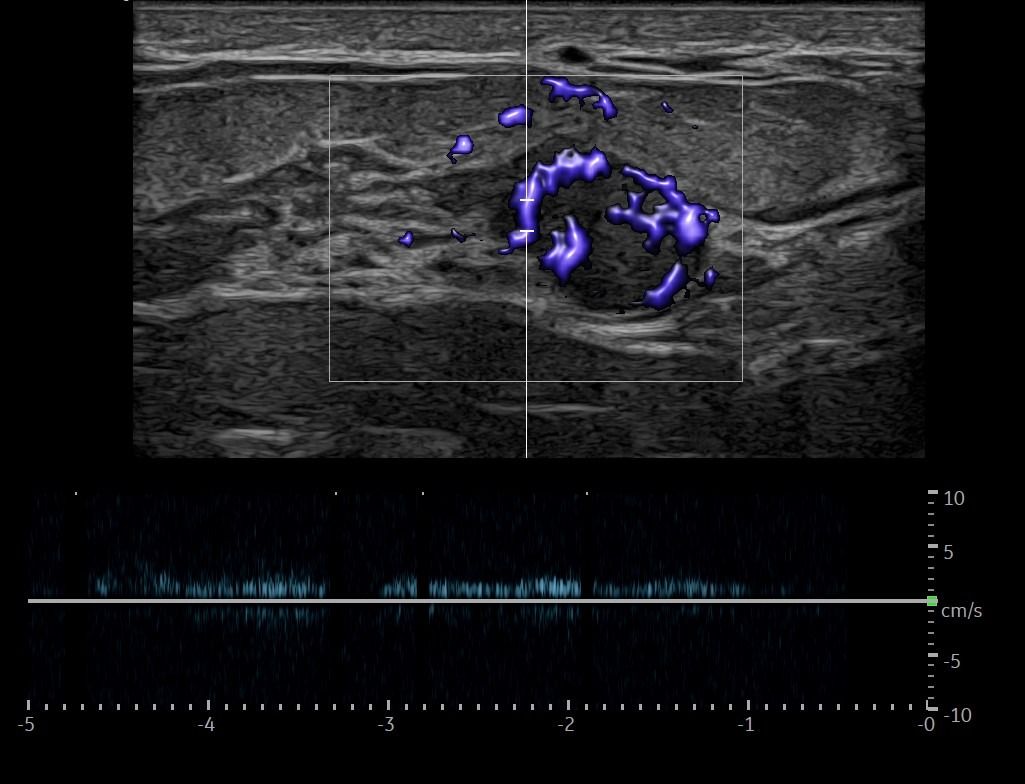

Modern ultrasound machines, equipped with advanced high-frequency transducers, techniques such as Color Doppler, Power Doppler, B-Flow, and Elastography, allow the analysis of breast architecture with exceptional accuracy.

Elastography can highlight the elasticity of a lesion, indicating whether it is hard or soft. Through this technique, we can assess the nature of the lesion, providing indications of whether it is benign or malignant. Additionally, with the contribution of Color Power Doppler and B-Flow, we can monitor the vascular flow within the lesions, offering even more information about the type and nature of the abnormality.